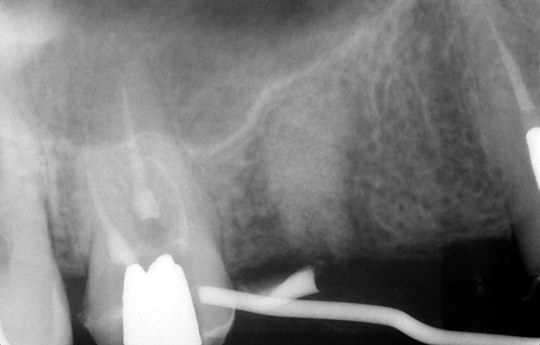

②抜歯同時骨造成

③埋入方向確認

歯科用CTとインプラントシミュレーションソフトによる事前の治療計画

また、事前検査にも負担軽減の工夫をしています。インプラントを埋め込むあごの骨には、重要な神経や血管があり、そこを誤って傷つけるようなことがあってはなりません。そのような危険性をできる限り少なくするためには、術前の精密な検査や診断が重要となります。そこでCTによる検査を行うことで、手術中の事故を防ぎ、より安全に治療を行えるよう努めているのです。

検査器具やレントゲン、CTで、歯やあごの骨の状態を調べます。